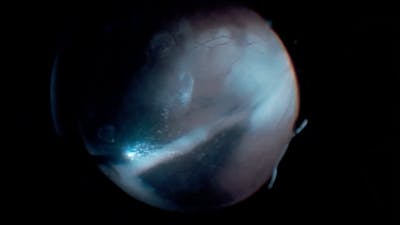

The RETINAWS panel led by Kourous Rezaei, MD, discuss techniques for vitreoretinal surgery and rare surgical cases.